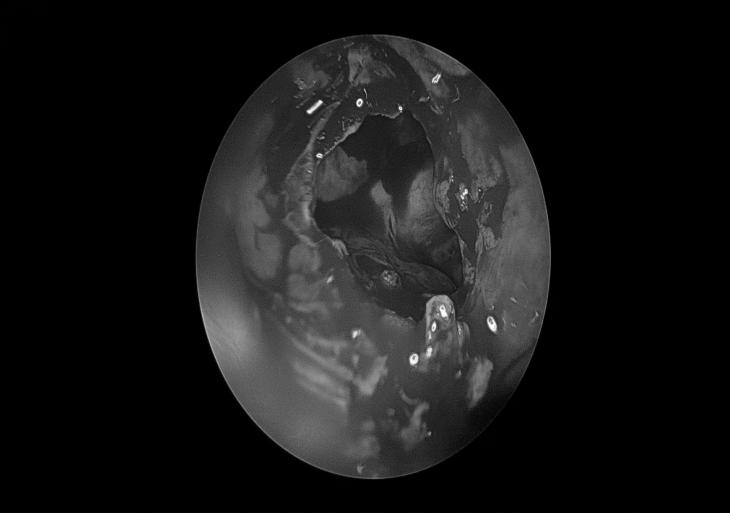

电子喉镜检查

左侧鼻腔

右侧鼻腔

鼻咽部

声门